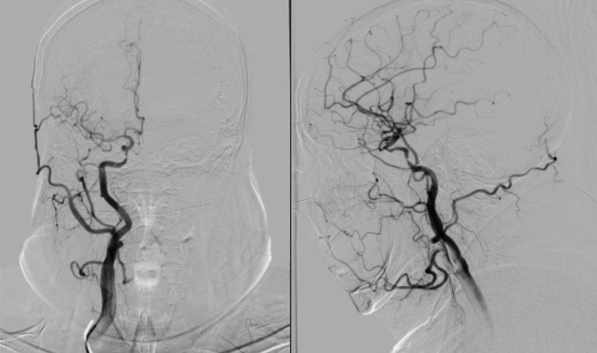

术后影像及检查

影像结论:术后残余狭窄小于 10%。

导丝怎么扩【载药时代 球扩天下】NOVA DES®颅内药物洗脱支架在颈内动脉颅内段重度狭窄中的应用体会二例!_https://www.jmylbn.com_新闻资讯_第30张